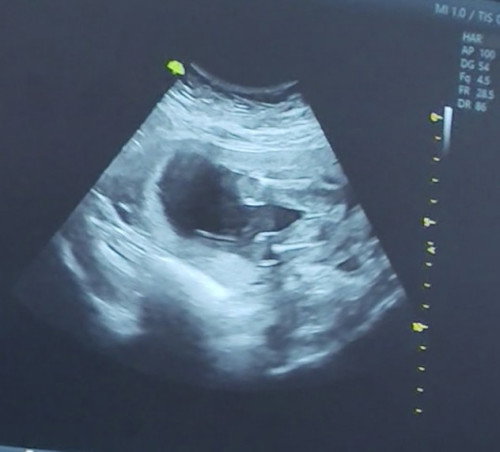

Nagpagender ako khapon 19wks na sabi babae pero nkadapa kasi c baby at diko din nkita yung genital pwede kayang mali ang sonologist my alam ba kyo na nagkamali na ang sono? Thanks panganay ko kc bby girl na sana itong bunso boy naman kasi CS ako hirap manganak high risk pa. Thanks po sa sasagot. #19_weeks1day